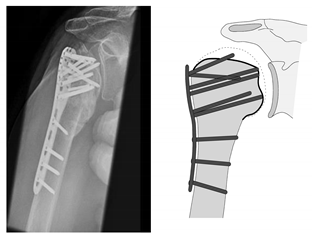

| Complication Type | Exemplary Images by X-rays or Pattern Images | Definition |

|---|---|---|

| 2b | ![]() | Complication Type 2b is limited to displacement of the greater tuberosity, lesser tuberosity, or both tuberosities. |

| 2c | ![]() | Type 2c is defined by a severe varus displacement (>20°) of the humeral head, which is associated with a screw cutout at the humeral head in parallel to Type 2a. In contrast to Type 2a, this varus displacement is characterized by an unstable osteosynthesis situation and progression. |